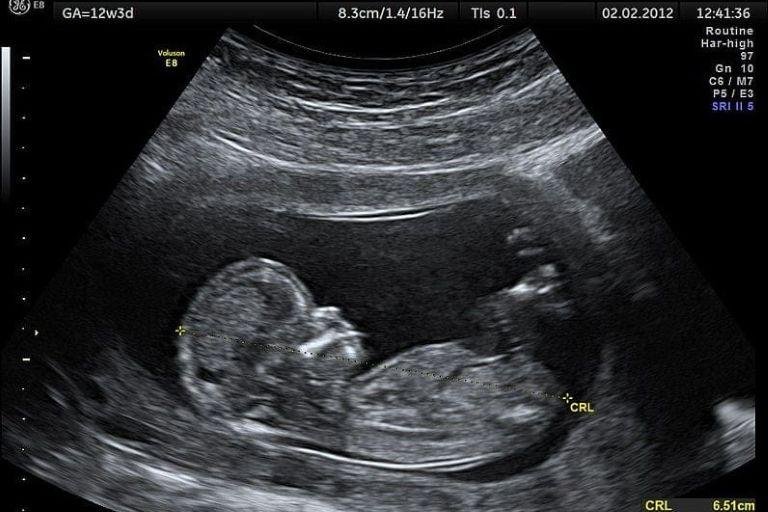

• Ultrassom Obstétrico

Acompanhamento completo da gestação com exames de alto e baixo risco, incluindo ultrassom obstétrico simples, com Doppler, Doppler com perfil biofísico fetal (PBF) e ultrassom morfológico do 1º, 2º e 3º trimestre.